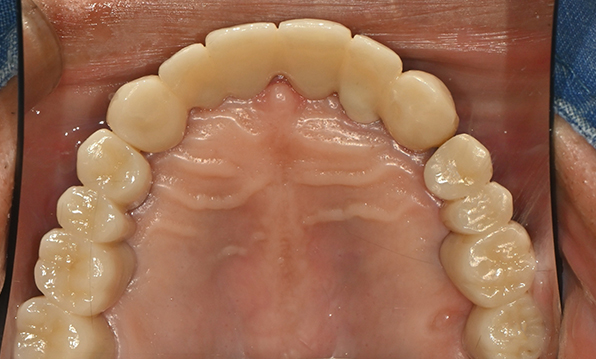

전체 임플란트

위 아래 치아가 정확하게 맞아야하는 고난이도 임플란트

임상 경험이 많은 숙련된 전문의의 섬세한 기술력이 중요합니다.

치료기간 : 2021.04.12~2021.09.15